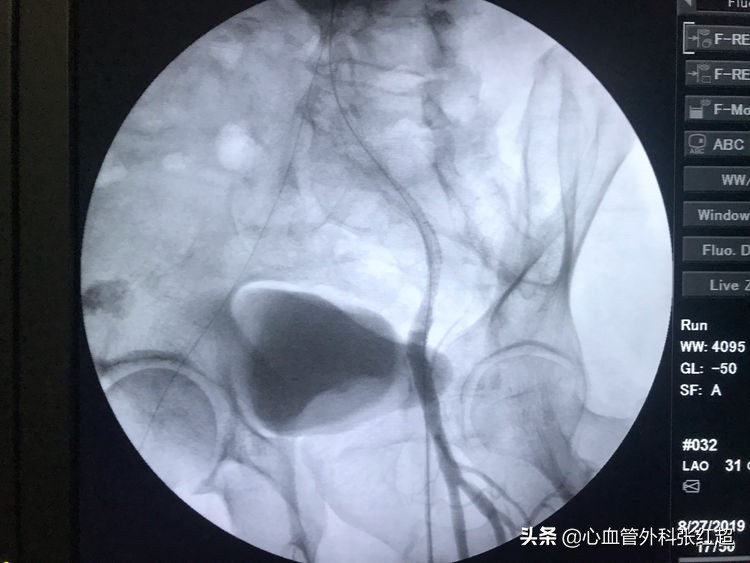

血管造影剂排空快,对侧显影淡,说明血管内血流速度快。

屈曲部稍有残余狭窄。不用硬扩,支架可以在术后贯性序扩。

放两枚支架更容易保证远端释放到位